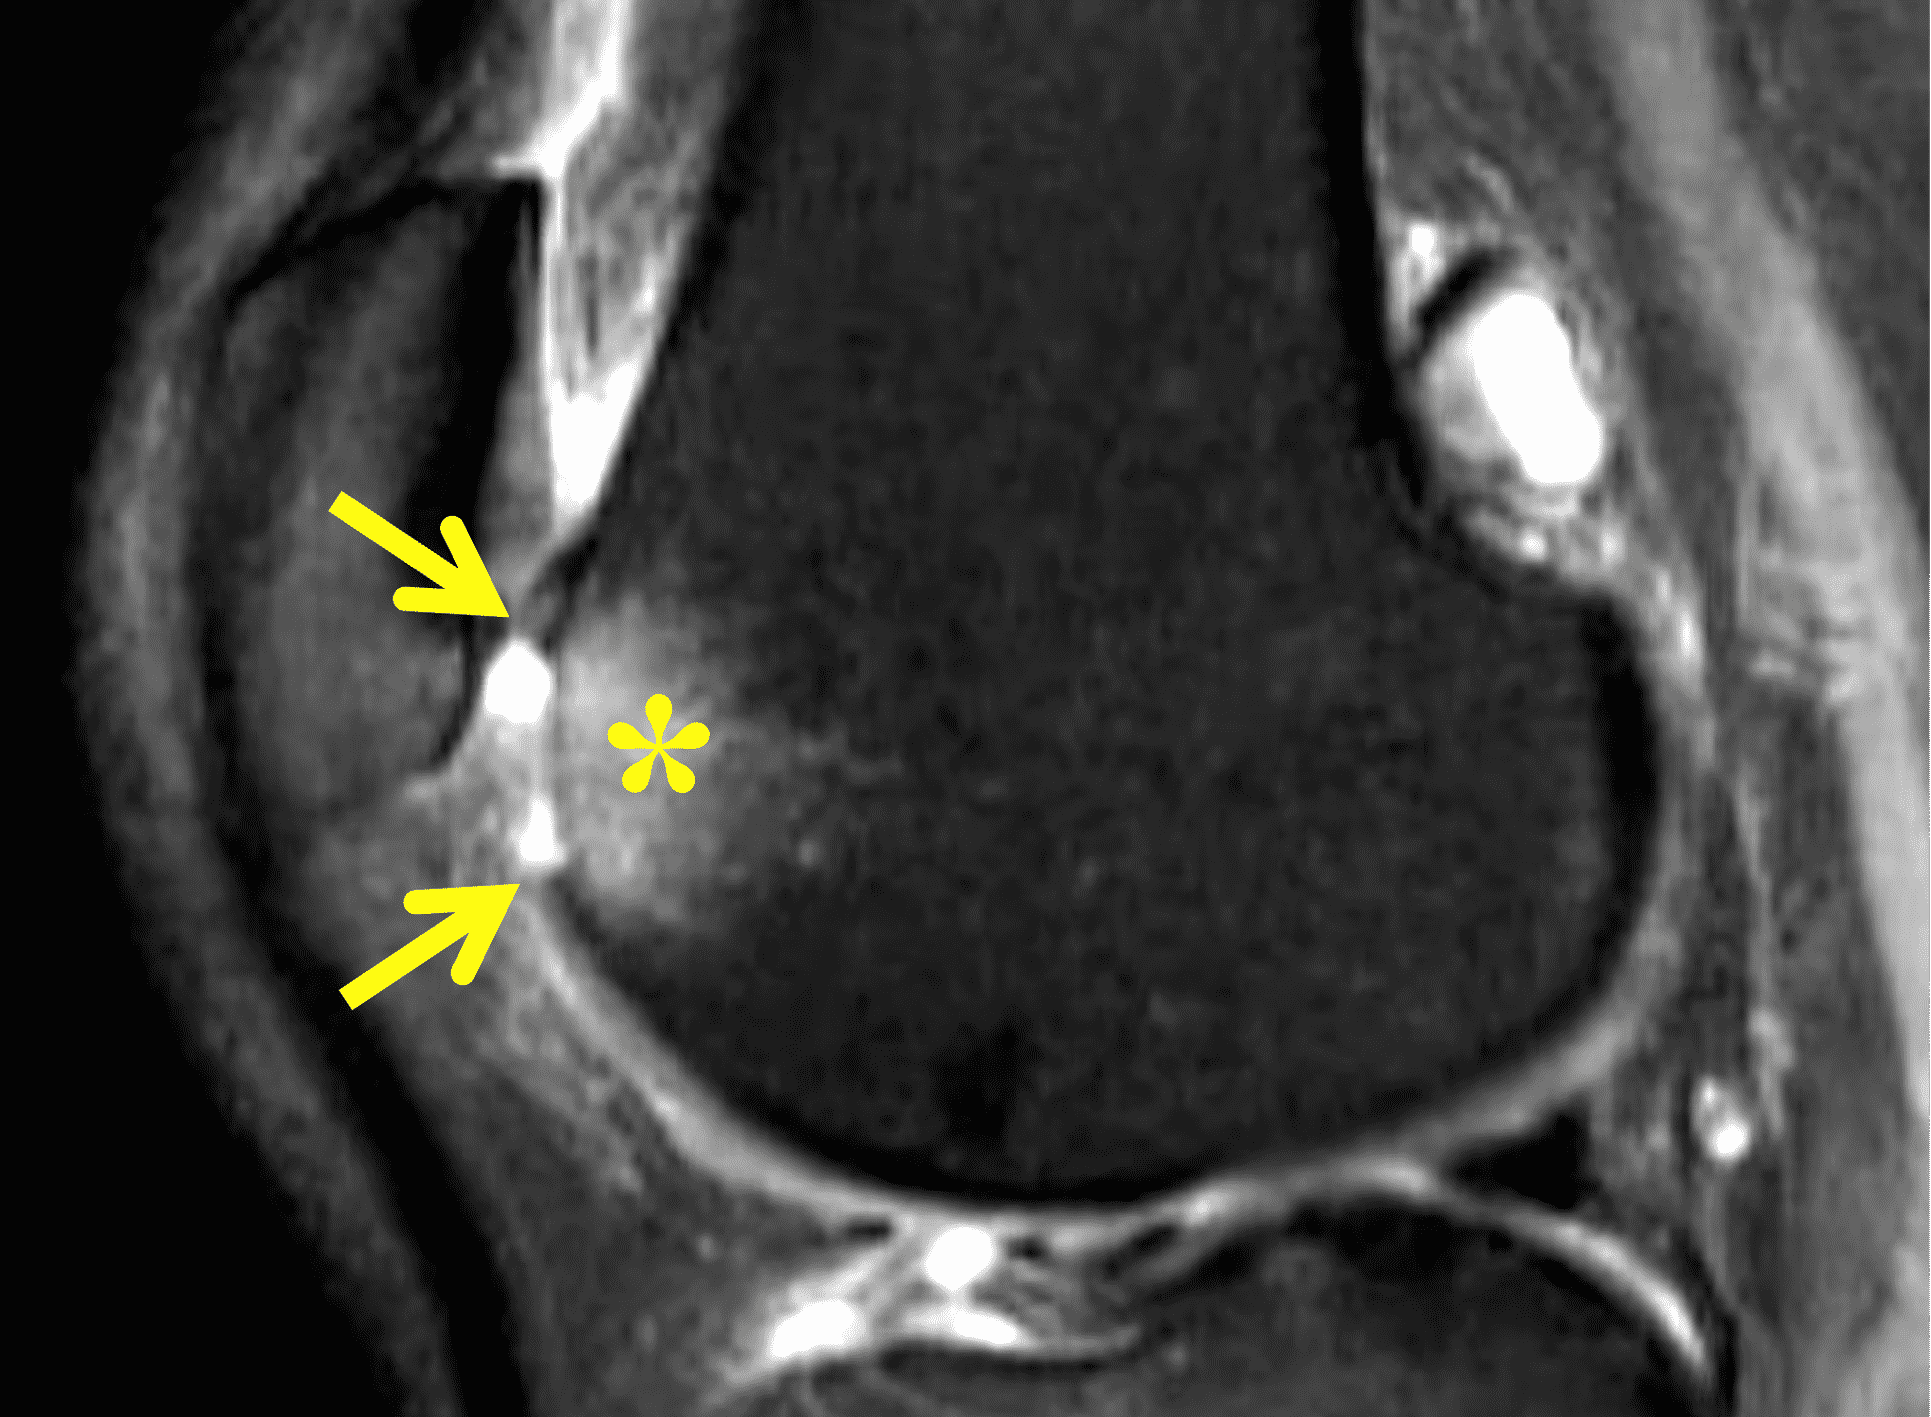

Articular cartilage is susceptible to both traumatic and degenerative lesions, but restoration procedures work best for traumatic lesions. Direct impaction, shear, and twisting mechanisms can injure the articular cartilage.3 Traumatic lesions include chondral fractures, which have a characteristic appearance on MRI characterized by a sharp transition between the lesion and surrounding normal cartilage with the walls of the defect oriented perpendicular to the articular surface (Figures 3A and 3B). Defects are often full thickness, extending to the subchondral bone plate. Subchondral marrow edema is common.4 An unstable cartilage fragment may be present in the crater or displaced as a loose body in the joint. Chondral flaps appear similar to chondral fractures but remain attached to the surrounding cartilage along one side of the lesion, which can act as a hinged trap door (Figures 3C and 3D). The two types of traumatic lesion often coexist, with a chondral fracture frequently demonstrating unstable flap(s) in its periphery (Figures 3E and 3F).

Figure 3: Examples of cartilage injuries amenable to restoration procedures. (3A) Drawing and (3B) sagittal fat-suppressed fluid-sensitive image showing a chondral fracture with vertical walls perpendicular to the articular surface (arrows), sharply demarcating the crater from the surrounding normal cartilage, and focal subchondral marrow edema (asterisk). (3C) Drawing and (3D) axial fat-suppressed fluid-sensitive image showing a chondral flap with a vertical wall on one side of the lesion (red arrow) and a intact, hinged bridge of cartilage on the other, with a full-thickness defect in between (yellow arrow). (3E) Sagittal T2-weighted image of a combined chondral fracture and flap. The chondral fracture has sharp margins (yellow arrows) with the surrounding intact cartilage, while a delaminating flap (black arrow) is present along the posterior lesion margin. (3F) Corresponding arthroscopic picture. The subchondral bone plate is exposed at the base of the lesion (asterisk), with a delaminating flap in the lesion periphery (arrow). C = normal surrounding cartilage.